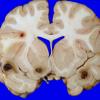

NEOPLASMS (HEMATOLYMPHOID)

Granulocytic Sarcoma